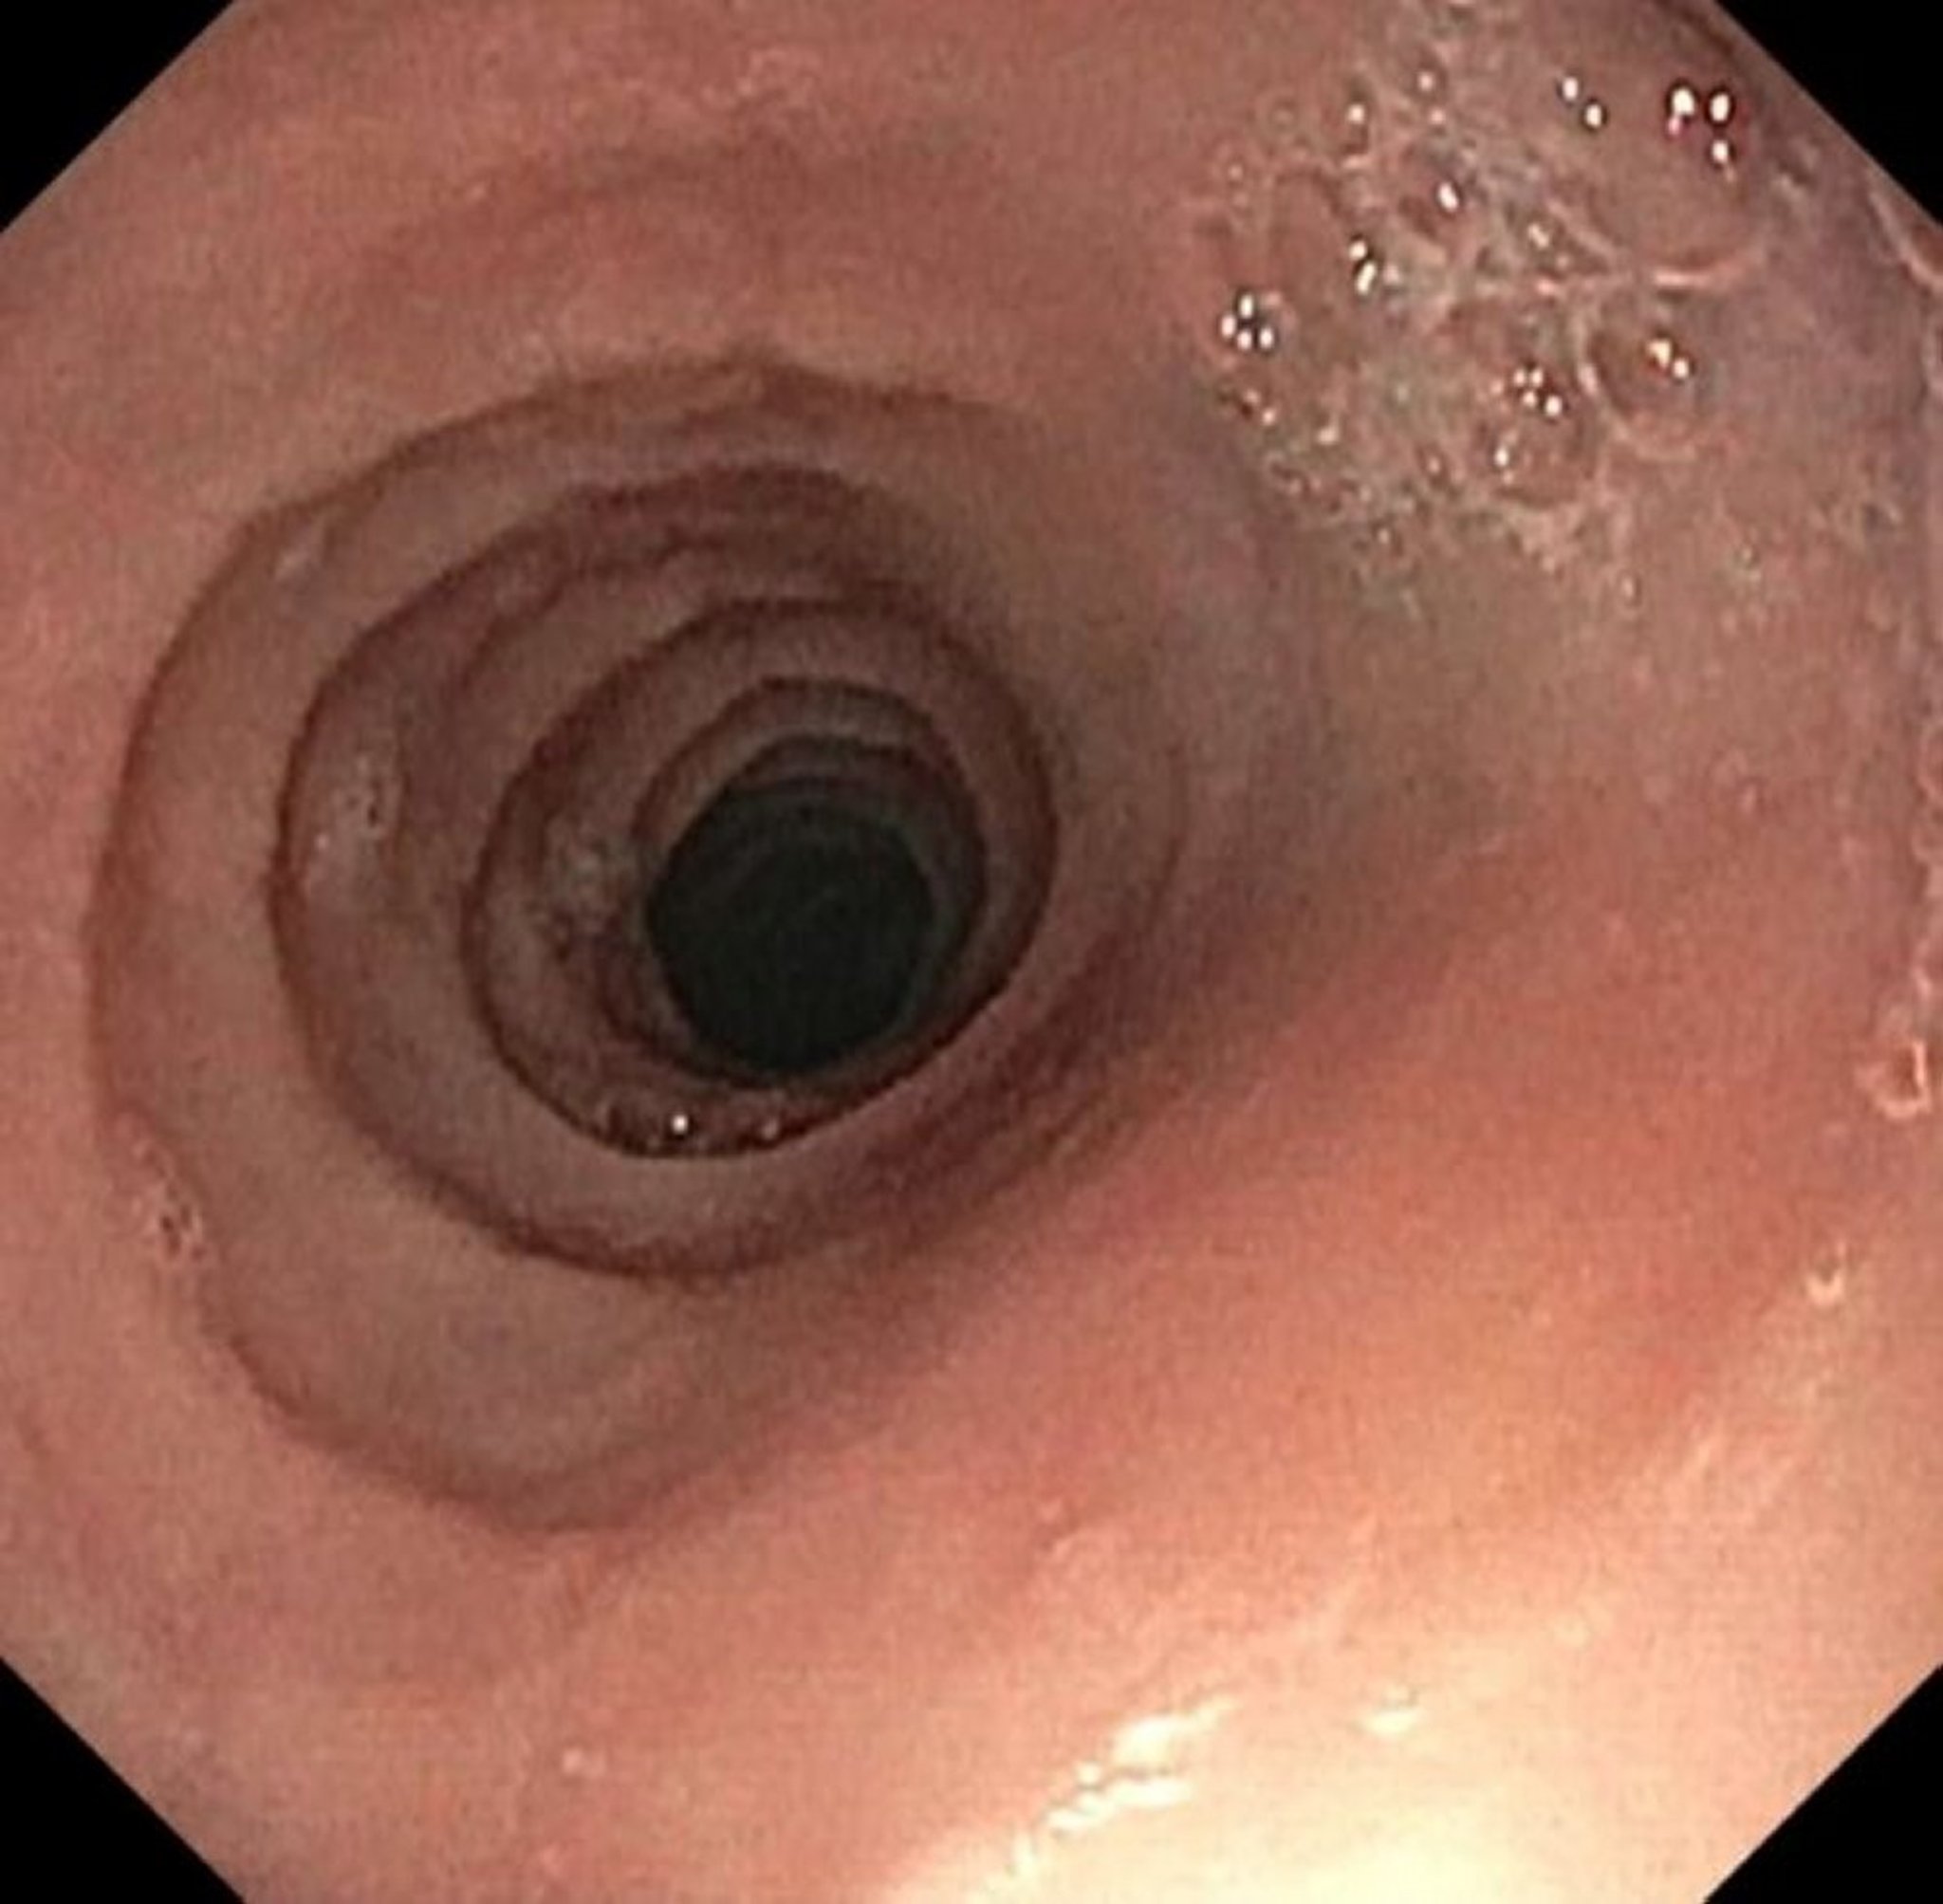

Rings and Strictures in Eosinophilic Esophagitis

Image provided by Kristle Lynch, MD.